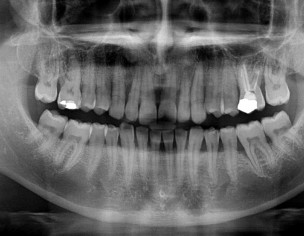

Needs clinical examination. on X-ray Examination RCT Of Upper 1-1 and splinting of teeth followered by deep curettage

I second Prof .asif are the steps initially we take to secure peridontally compromised mobile teeth .

I also see start of periapical infection in front teeth .

I must say to take one CBCT or periapical Xray for confirm diagnosis of infection .